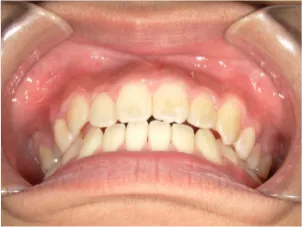

小学5年生の出っ歯、過蓋咬合の治療

治療前①小5:スタート

| はじめのご相談 | 凸凹になりそうと一般歯科の先生に言われたのでみてほしい |

|---|---|

| カウンセリング・診断結果 | 下あごが後退しているタイプの出っ歯で、過蓋咬合で下あごが前に成長しにくいタイプの顔立ちです。 上の歯列弓が小さめで前歯に凸凹があります。 口元が閉じにくい口唇閉鎖不全があります。 *上記に対する治療の流れを説明し(拡大・前歯の並べ替え→出っ歯の改善→モノブロック装置(筋機能的咬合誘導装置)→必要によりマルチブラケット法)、以下の治療を提案しました。 |